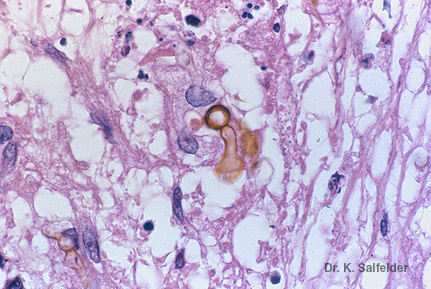

Abb. 13,18: Phaeohyphomykose

Phialophora verrucosa bildet in diesem Fall im Gewebe gelbe Hyphen und Pseudohyphen